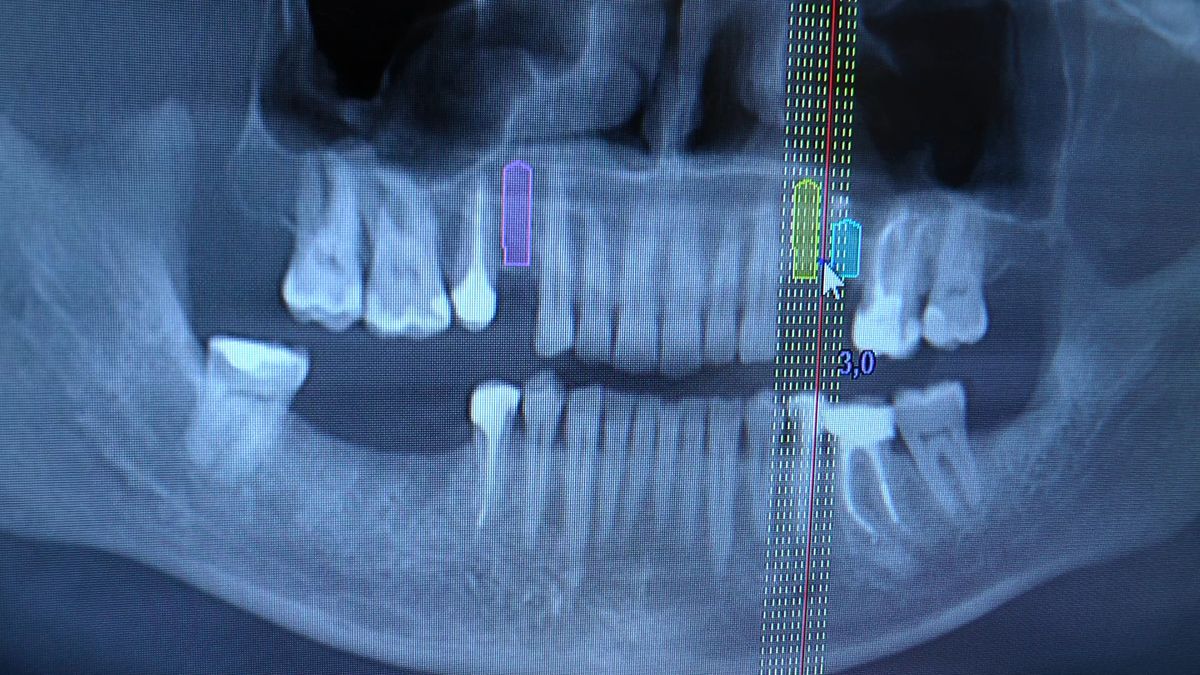

Pierwszy weekend 2019 roku w Instytucie Vivadental, to doskonałe otwarcie kolejnego roku edukacyjnego i szkolenia naszych Kursantów. W drodze do sukcesu w implantologii zdobywają wiedzę i umiejętności, a każdy kolejny zabieg to impuls i inspiracja do twórczego rozwoju w leczeniu własnych Pacjentów. Rozpoczęliśmy od sesji praktycznej implantologicznej właśnie z udziałem Pacjentów, na której dominowały samodzielne zabiegi wykonywane pod kierunkiem Mentorów – dr n.med. Violetty Szycik i dr n.med. Magdaleny Kisłowskiej – Syryczyńskiej. W ciągu dwóch dni zabiegowych przyjęliśmy 14 Pacjentów, przeprowadziliśmy zabiegi chirurgiczne, zabiegi regeneracyjne tkanki kostnej i augmentacji oraz wszczepiliśmy 20 implantów systemu Axiom. W ramach panelu edukacyjnego Sukces Twojego Biznesu odbyły się kolejne zajęcia z NLP, na których nasz Mentor Mariusz Wójcik z Gdańskiej Akademii Umiejętności Menedżerskich, kontynuował wprowadzenie do psychologii i podstaw kierujących decyzjami Pacjentów. Ćwiczenia w wesołej i koleżeńskiej atmosferze były niezwykle pouczające, a jednocześnie stanowiły idealną odskocznię po wyczerpujących zabiegach.